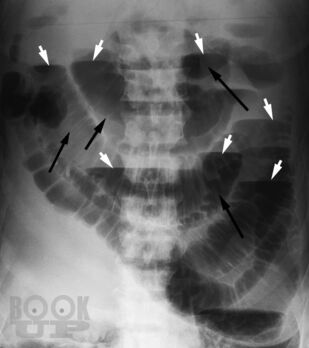

Учебно-методическое пособие разработано для подготовки к занятиям по лучевой диагностике заболеваний органов ЖКТ. В пособии рассматриваются всесторонние аспекты методов лучевой диагностики при подозрении на острое хирургическое заболевание органов ЖКТ, в частности кишечную непроходимость, прободение полого органа, нарушение брыжеечного кровообращения и др.